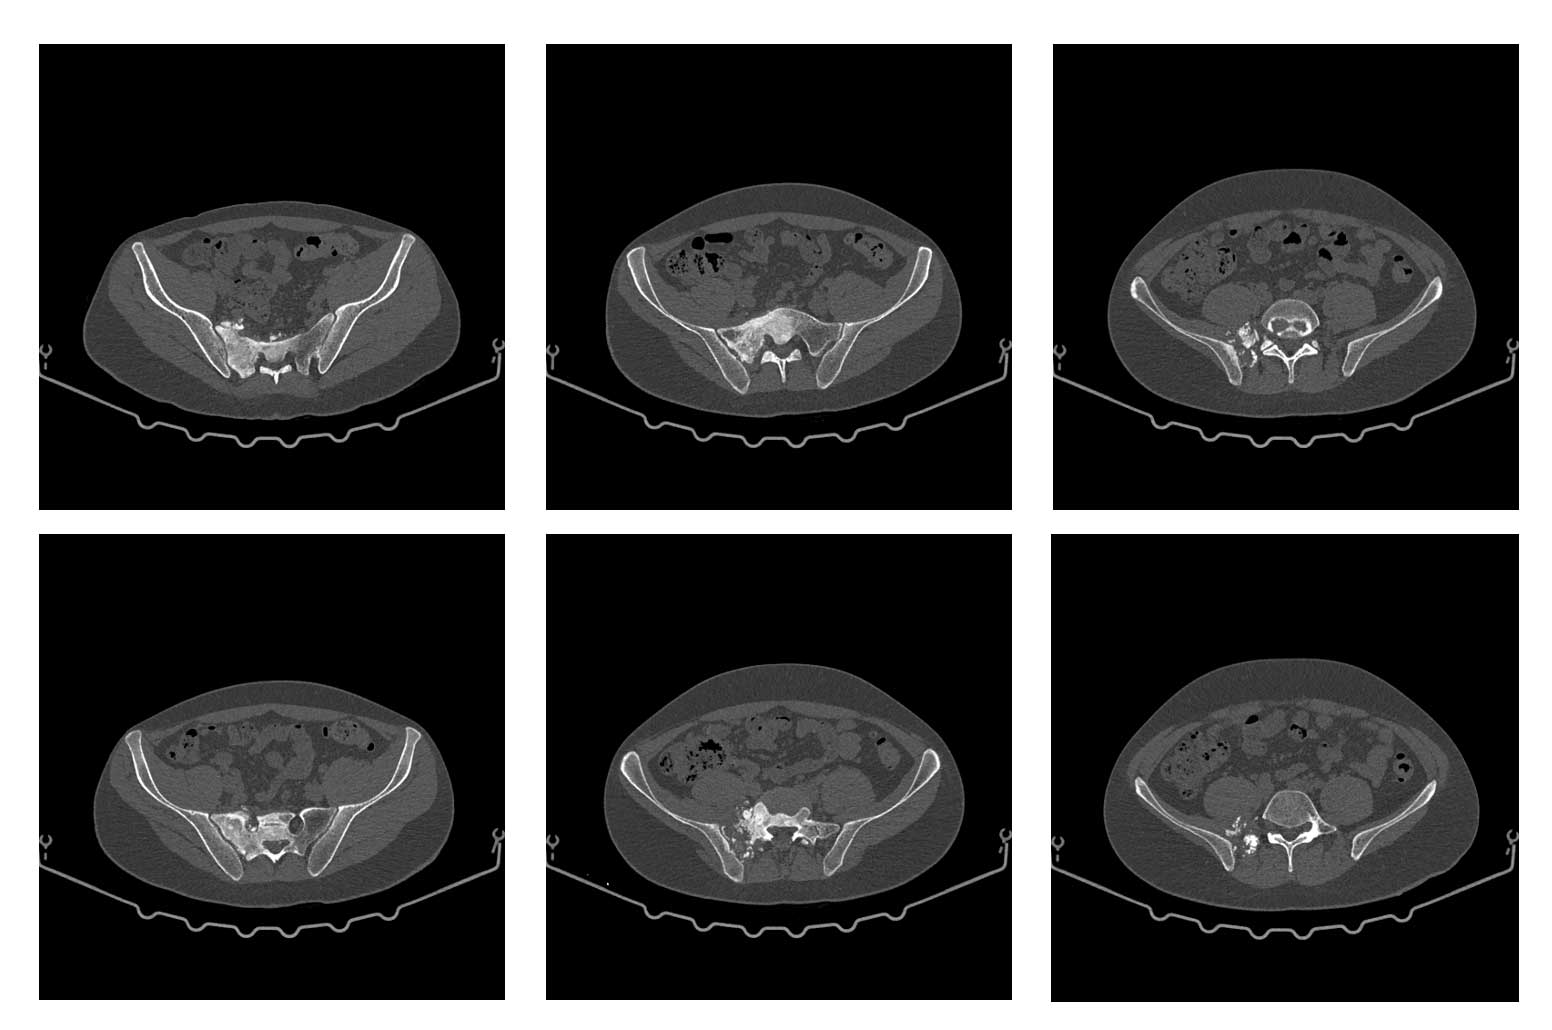

Ameliyat öncesi: Tomografide sağ sakroiliak bölgede düzensizlik ve sklerozun eşlik ettiği tümör dokusu görülmekte.

Ameliyat öncesi:Tomografide sağ sakroiliak bölgede düzensizlik ve sklerozun eşlik ettiği tümör dokusu görülmekte.